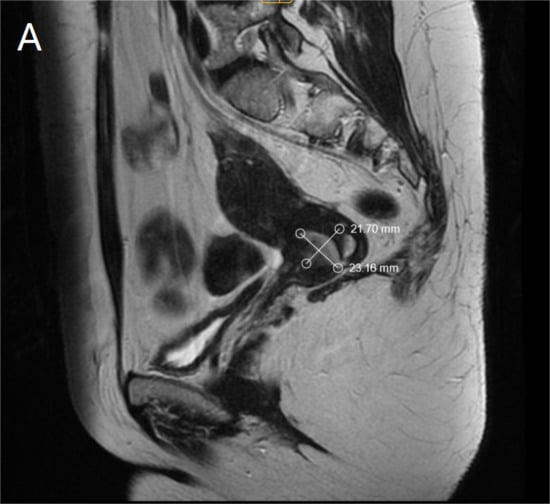

Ultrasound examination of the abdomen and pelvis revealed no abnormal findings, and lung radiography was normal. Preoperative magnetic resonance imaging (MRI) identified an infiltrative tumor measuring 23.69 × 21.70 mm, as demonstrated in Figure 1A,B.

Figure 1.

(A). MRI—Sagittal section of the tumor formation (B). MRI—Coronal section of the tumor formation.